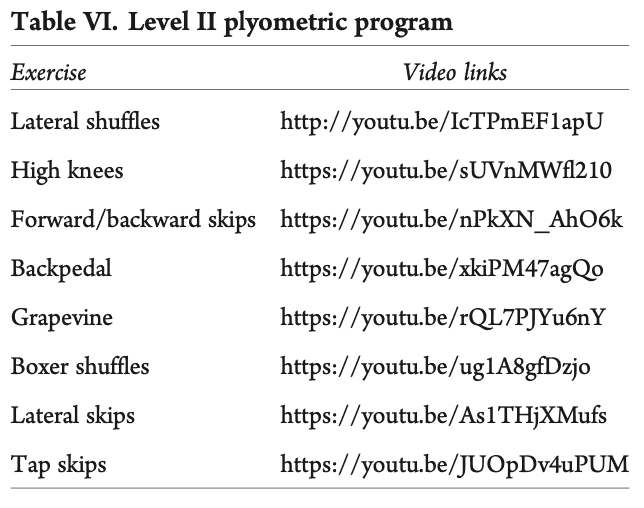

- Фаза 2 беше бърза реакция и плиометрична дейност. В тях се посочва следното: "Бързата мускулна реакция и плиометрията започват в тази фаза, като се стига до около 500-600 контакта между единия и двата крака. Така, ако средният оборот на бегача е 170-180 крачки в минута, за да достигне необходимите 500-600 контакта с един крак, ще е необходимо да бяга 5-7 минути."

Преминаването към програмата за ходене/бягане е разрешено, когато участниците са завършили успешно фаза 1 и плиометричната програма от ниво I на фаза 2, могат да ходят без да куцат и нямат болка при ежедневните дейности. И тук съветът беше тази програма да се започне на бягаща пътека. Трябваше да се спазват следните правила: (i) без хълмове и наклони, (ii) без работа за скорост, (iii) работа върху формата и (iv) бягане всеки втори ден. В идеалния случай те трябва да продължат плиометричната програма от II и III ниво.